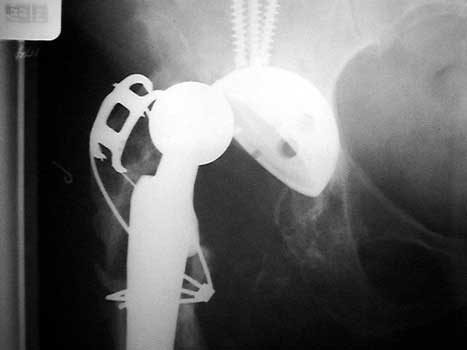

Dislocated femoral component related to non union of greater trochanteric osteotomy. Post operative radiograph with constraining ring about femoral head, which helps maintain head in cup. Greater trochanter resected.